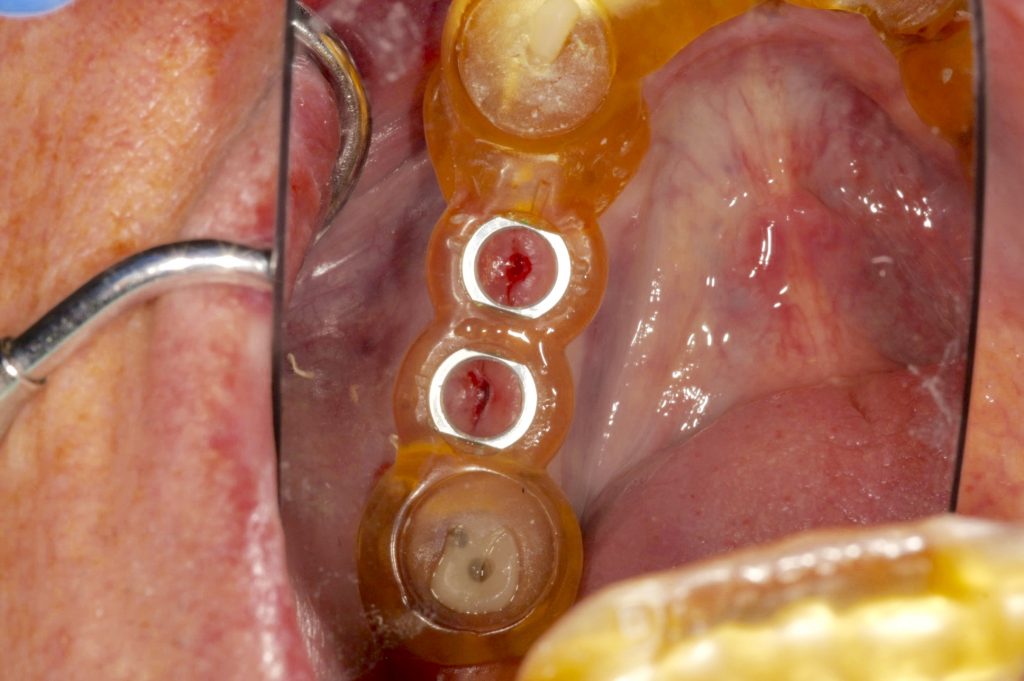

Autores: PRÓLOGO Asimismo, desde el punto de vista pedagógico, el profesional nobel en la materia tiene a su alcance la posibilidad de corregir cualquier posición implantaría en el ordenador, planear los provisionales y plasmarlos en la bio réplica antes de tocar al paciente a operar. Todos estos razonamientos nos llevan a presentar un caso de condiciones muy favorables para poner en práctica estos métodos como primer acercamiento a una Odontología Digital de alta calidad, con medios informáticos, que ya están presentes en la profesión de hoy en día, y será la protagonista única del futuro. Por otro lado, después de numerosos estudios que nos llevan a plantear el “gap” entre implante y pilar(abuttment), como principal responsable de la periimplantitis dado que la microbiota presente en el mismo es imposible de limpiar y en su presencia la cortical ósea reacciona reabsorbiéndose, nos ha llevado a utilizar implantes monobloc ya que los ejes implantarios y protéticos coincidían, y nos permitían su uso. Además, el circonio, ha mostrado a la luz de estudios muy recientes, una preservación y adhesión de los tejidos blandos superiores al titanio, tanto en su tratamiento de superficie de la rosca como a nivel gingival. DESARROLLO Paciente varón de 68 años, con antecedentes de radio/quimioterapia cinco años antes, con Rehabilitación Oral de los cuatro cuadrantes, con una Oclusión Mutuamente Compartida conservada, (REF.8) la que fracasa en el cuadrante 4, 19 años después. El mismo presentaba un puente de porcelana sobre circonio con pilares en 44 y 47, reemplazando el edentulismo de 45 y 46. Se produce la fractura del PM del 44, y ante una endodoncia antigua y corta, se decide implantar las zonas edéntulas, conservando temporariamente los pilares, hasta producida la oseointegración, para entonces también exodonciar el 44. DIAGNÓSTICO Tomamos impresiones del maxilar antagonista, Arco Facial Estático y realizamos montaje del mismo mediante la sistemática ARTEX. Producimos la relajación del músculo Pterigoideo Externo, para obtener la ORC (Oclusión en Relación Céntrica) mediante el método de Laminillas de Long, basado en el concepto de INERVACIÓN RECÍPROCA. Esto nos permitirá montar el maxilar inferior, tanto en su forma de: La primera para practicar la cirugía guiada y comprobar su eficacia, y el modelo de yeso para ser escaneado y confeccionar la GUÍA QUIRÚRGICA. La Biorréplica la obtenemos transformando los archivos DICOM que nos da el CBCT en archivos STL, y a partir de ellos, mediante una tecnología de PROTOTIPADO RÁPIDO, la obtención de un objeto físico en 3D a través de la aglutinación selectiva de una sucesión de capas de polvo. Procedemos a montar la biorrèplica y el modelo de yeso del caso. Podemos verificar la exactitud de las medidas del hueso residual en la bio réplica y compararlas con el scanner. Arrojando un resultado de 8,5 mm de cortical externa a cortical externa. Pudiendo también medir la distancia hasta el dentario. y comparar gracias a la ventana lateral de la biorréplica Dándonos 22mm de distancia. Con lo cual deducimos que implantes de 4,1mm por 12 mm serán perfectamente rodeados de hueso. Medimos también la distancia desde oclusal del antagonista, hasta el hueso desnudo. Lo mismo que, mediante la utilización de la guía radiológica, con un material radiolúcido colocado en gingival de la misma, podemos medir la altura de la encía. Con lo cual podemos calcular la altura del pilar. Es entonces cuando con el programa COC Diagnostix se realiza la programación final: Obteniendo no solo la ubicación, largo, ancho y ángulo de los implantes sino también los provisionales mediante CAD CAM. Ya entonces podemos hacer la práctica quirúrgica en la bio réplica, mediante la guía quirúrgica, instalando los implantes de prueba que no serán los de circonio, ya que la casa no cuenta con ellos, pero si otros de las mismas dimensiones. TRATAMIENTO Entramos ya en la cirugía propiamente dicha. Antisepsia de la zona a operar y zonas anexas. Comprobación del perfecto ajuste e inmovilidad de la G.Q. en boca durante la cirugía. Marcado de la encía y perforación de la cortical. Visión a través de la Guía de la mínima intervención anterior. Comprobación sin Guía. Incisión mínima mesio distal, para apartar y conservar encía queratinizada. Secuencia de drills, perforando a profundidad requerida Observación del Mínimo Trauma Implantes Strauman de Zirconio Monoblock en blíster y montádo en contrángulo reductor. Instalación controlando torque con contrángulo reductor. Comprobación clínica. Comprobación Radiográfica y con Guía. Toma de impresiones, y armado de modelos con técnicas de pasividad protética. Montaje. Resultado de las provisionales ejecutadas por CAD CAM Al no estar conformes con el resultado decidimos desechar dichas provisorias y optar por repetirlas. Nuevas provisorias realizadas mediante encerado convencional. Estado de los tejidos blandos. Provisorias en boca. Oclusión de Estímulo Inmediato. Ref.10: Carga inmediata .Alberto y Diego Bechelli. Comprobación mediante CBCT post operatorio Componentes del equipo (En la próxima presentación, mostraremos las coronas definitivas de porcelana sobre circonio, y la desoclusión provocada por una OCLUSIÓN MUTUAMENTE COMPARTIDA, sobre estos implantes y otros seis mas) REFERENCIAS

FIG: 21-22-23-24-25-26

Fig. 21

Fig. 22

Fig. 23

Fig. 24

Fig. 25

Fig. 26

FIG:42-43-44-45-46

Fig. 42

Fig. 43

Fig. 44

Fig. 45

Fig. 46

FIG:47-48-49

FIG:50-51-52-53-54